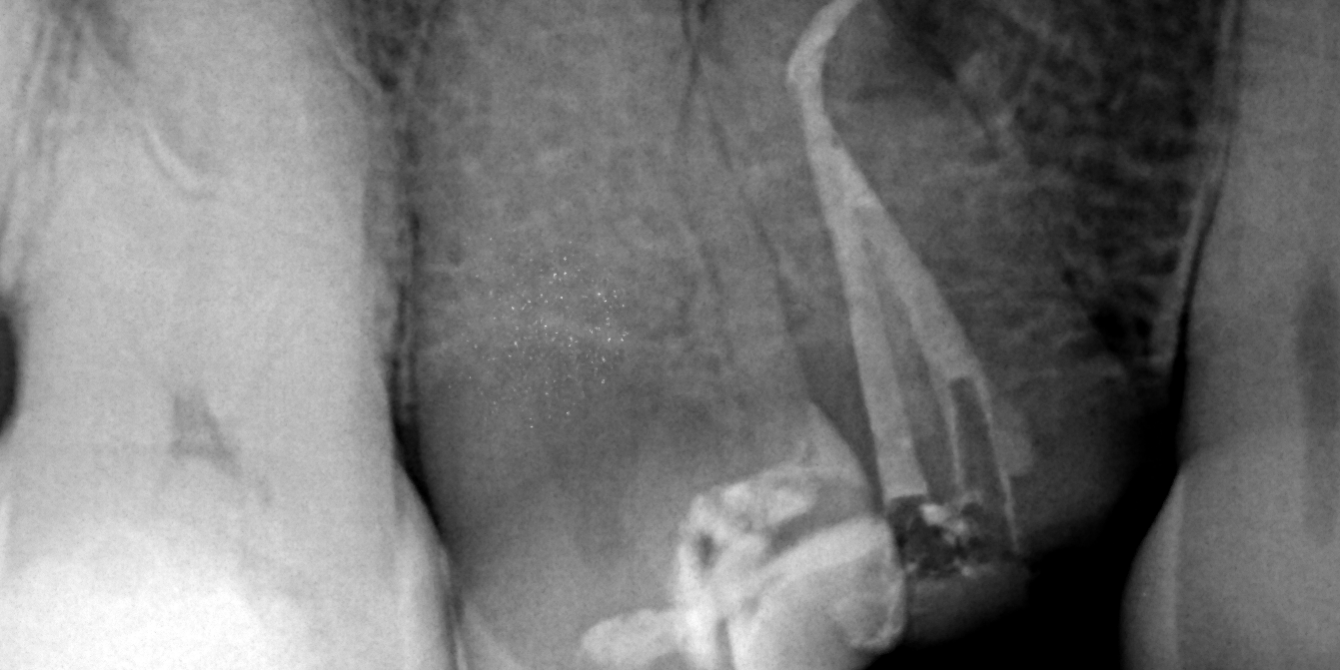

Canal Sealing with NeoSealer Flo®️:

Canal obturation was performed using NeoSealer Flo®️ cement and gutta-percha with continuous wave technique. This combination ensures a hermetic tridimensional seal, preventing reinfection and promoting periapical healing.